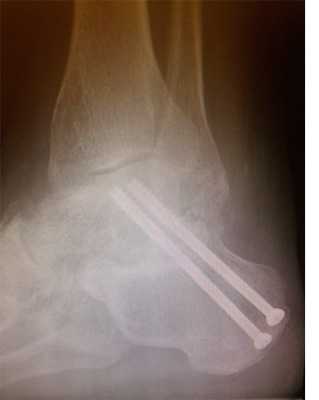

Пациент М. 1980 г.р., травму получил при падении на стопы с высоты 1,5 метра. Лечился по месту жительства (в травмпункте районной больницы) консервативно в гипсовой повязке в течение 14 дней. Консультирован в травматологическом отделении ФГБУ «УНИИТО им. В.Д. Чаклина» Минздрава РФ, предложено оперативное лечение. При поступлении кожные покровы стопы чистые, без признаков воспаления и сдавления тканей. Стопа отечна, уплощена. На рис. 1 представлены рентгенограммы пациента. Прооперирован через 2 недели после травмы. Операция состоит из двух этапов. Первый этап заключается в наложении дистракционного аппарата. Проводятся две спицы 1,8 мм во фронтальной плоскости: первая через нижнюю треть диафиза большеберцовой кости, вторая через бугор пяточной кости (рис. 2). Спицы фиксируются в дистракционном аппарате, выполненном из двух полуколец, соединенных между собой двумя телескопическими тягами. Особое расположение полуколец, фиксация спиц на концах полуколец, крепление кронштейнов для телескопических тяг обеспечивает тракцию пяточной кости в необходимом направлении с использованием минимального количества спиц и внешних опор при сохранении необходимого поля обзора для проведения рентгенологического и визуального контроля репозиции и фиксации. Второй этап - закрытая элевация импрессированной суставной поверхности и окончательная репозиция пяточной кости. Через разрез длиной до 1 см по латеральному краю ахиллова сухожилия (рис. 3) в месте его прикрепления к пяточной кости под соответствующий фрагмент подводится элеватор (рис. 4), манипуляцией которым устраняется смещение и выполняется провизорная фиксация спицами 1,5 мм (рис. 5). При сагиттальном раскалывании суставной фасетки целесообразно проведение одного-двух винтов субхондрально (рис. 6). Стержень вводится с дорзальной поверхности пяточной кости по ее оси через разрез до 2 см по предварительно сформированному остеотомом каналу (рис. 7, 8). Далее через проколы кожи с помощью кондуктора (рис. 9) выполняется запирание винтами с латеральной поверхности, внешнее устройство демонтируется. Достигнуто удовлетворительное стояние отломков (рис. 10).

Рис. 10. На рентгенограмме левой стопы в прямой и боковой проекциях определяется удовлетворительное стояние костных фрагментов на фоне металлофиксатора